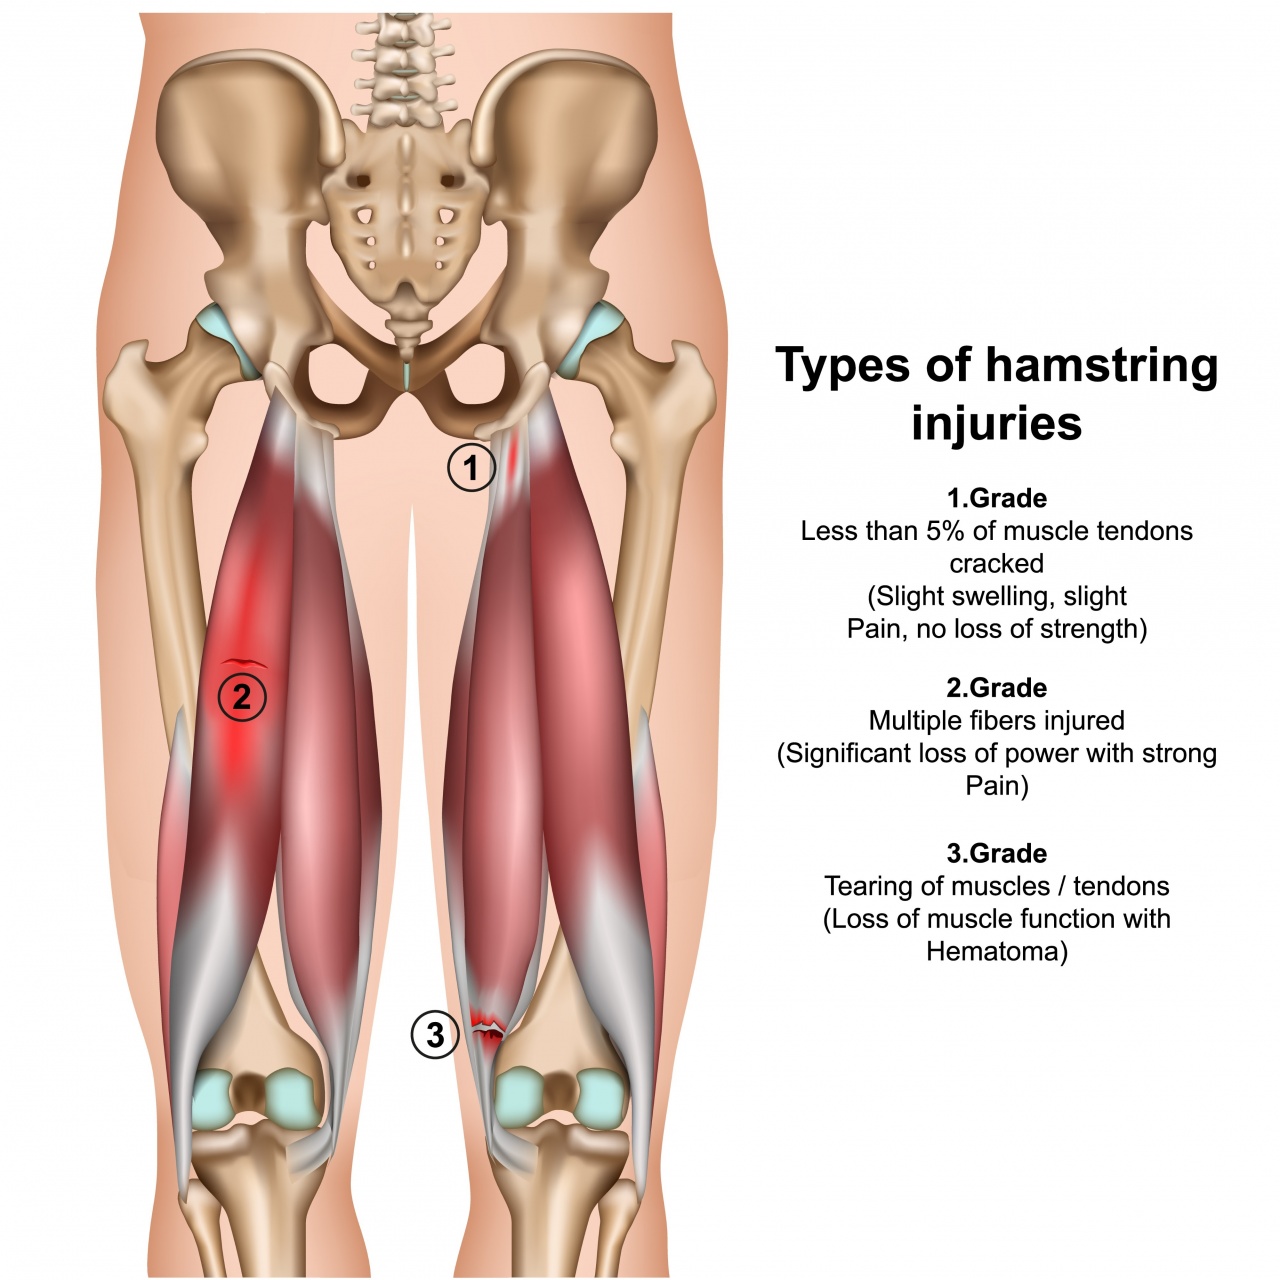

根据撕裂程度,临床通常分为三级。一级拉伤仅涉及少数肌纤维,康复期约7-14天;二级为部分撕裂,伴淤血与明显功能障碍,需3-6周恢复;三级为完全断裂,需手术且康复期超过3个月。